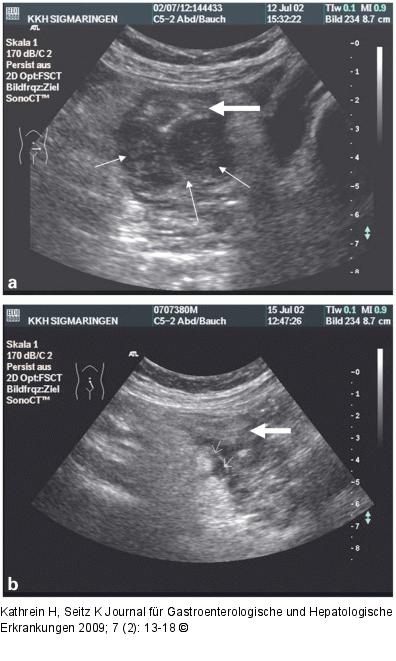

Abbildung 4a-b: Abszess Abszess (dünne Pfeile) bei Sigmadivertikulitis vor (a) und nach Punktion (b), Sigmaabschnitt (dicker Pfeil) |

Abszess (dünne Pfeile) bei Sigmadivertikulitis vor (a) und nach Punktion (b), Sigmaabschnitt (dicker Pfeil) |